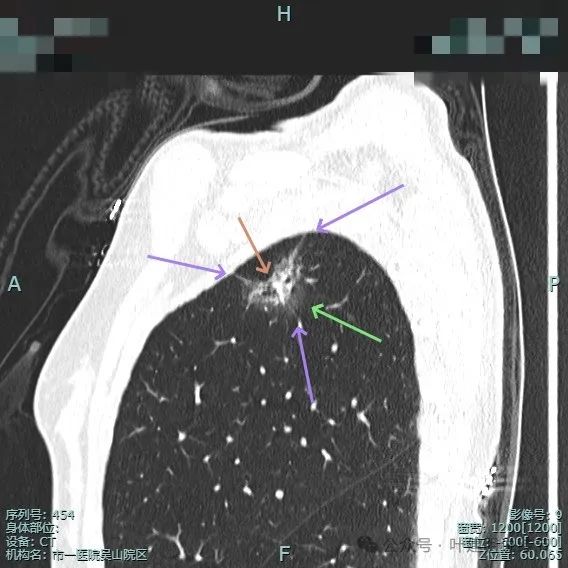

实性成分较明显,扩张的支气管壁显得僵硬,表面分叶明显,边缘细毛刺明显。

毛刺征、混合密度且实性成分杂乱、支气管扩张僵硬、分叶征明显。

血管进入、表面分叶、胸膜牵拉、磨玻璃成分明显、实性部分缺乏收缩力但显杂乱,整体轮廓与边界清。